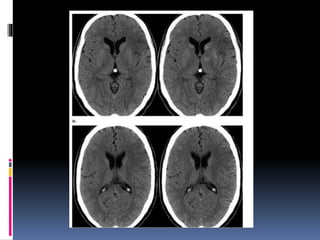

NECT shows hypodensity of the right basal ganglia compared to the normal.

pCT was performed CBV shows markedly reduced blood volume in the right basal

ganglia compared to the normal left side .

CBV in the cortex overlying the basal ganglia infarct appears relatively normal.

NECT shows hypodensityof the right basal ganglia compared to the normal. pCT was performed CBV shows markedly reduced blood volume in the right basal ganglia compared to the normal left side . CBV in the cortex overlying the basal ganglia infarct appears relatively normal.